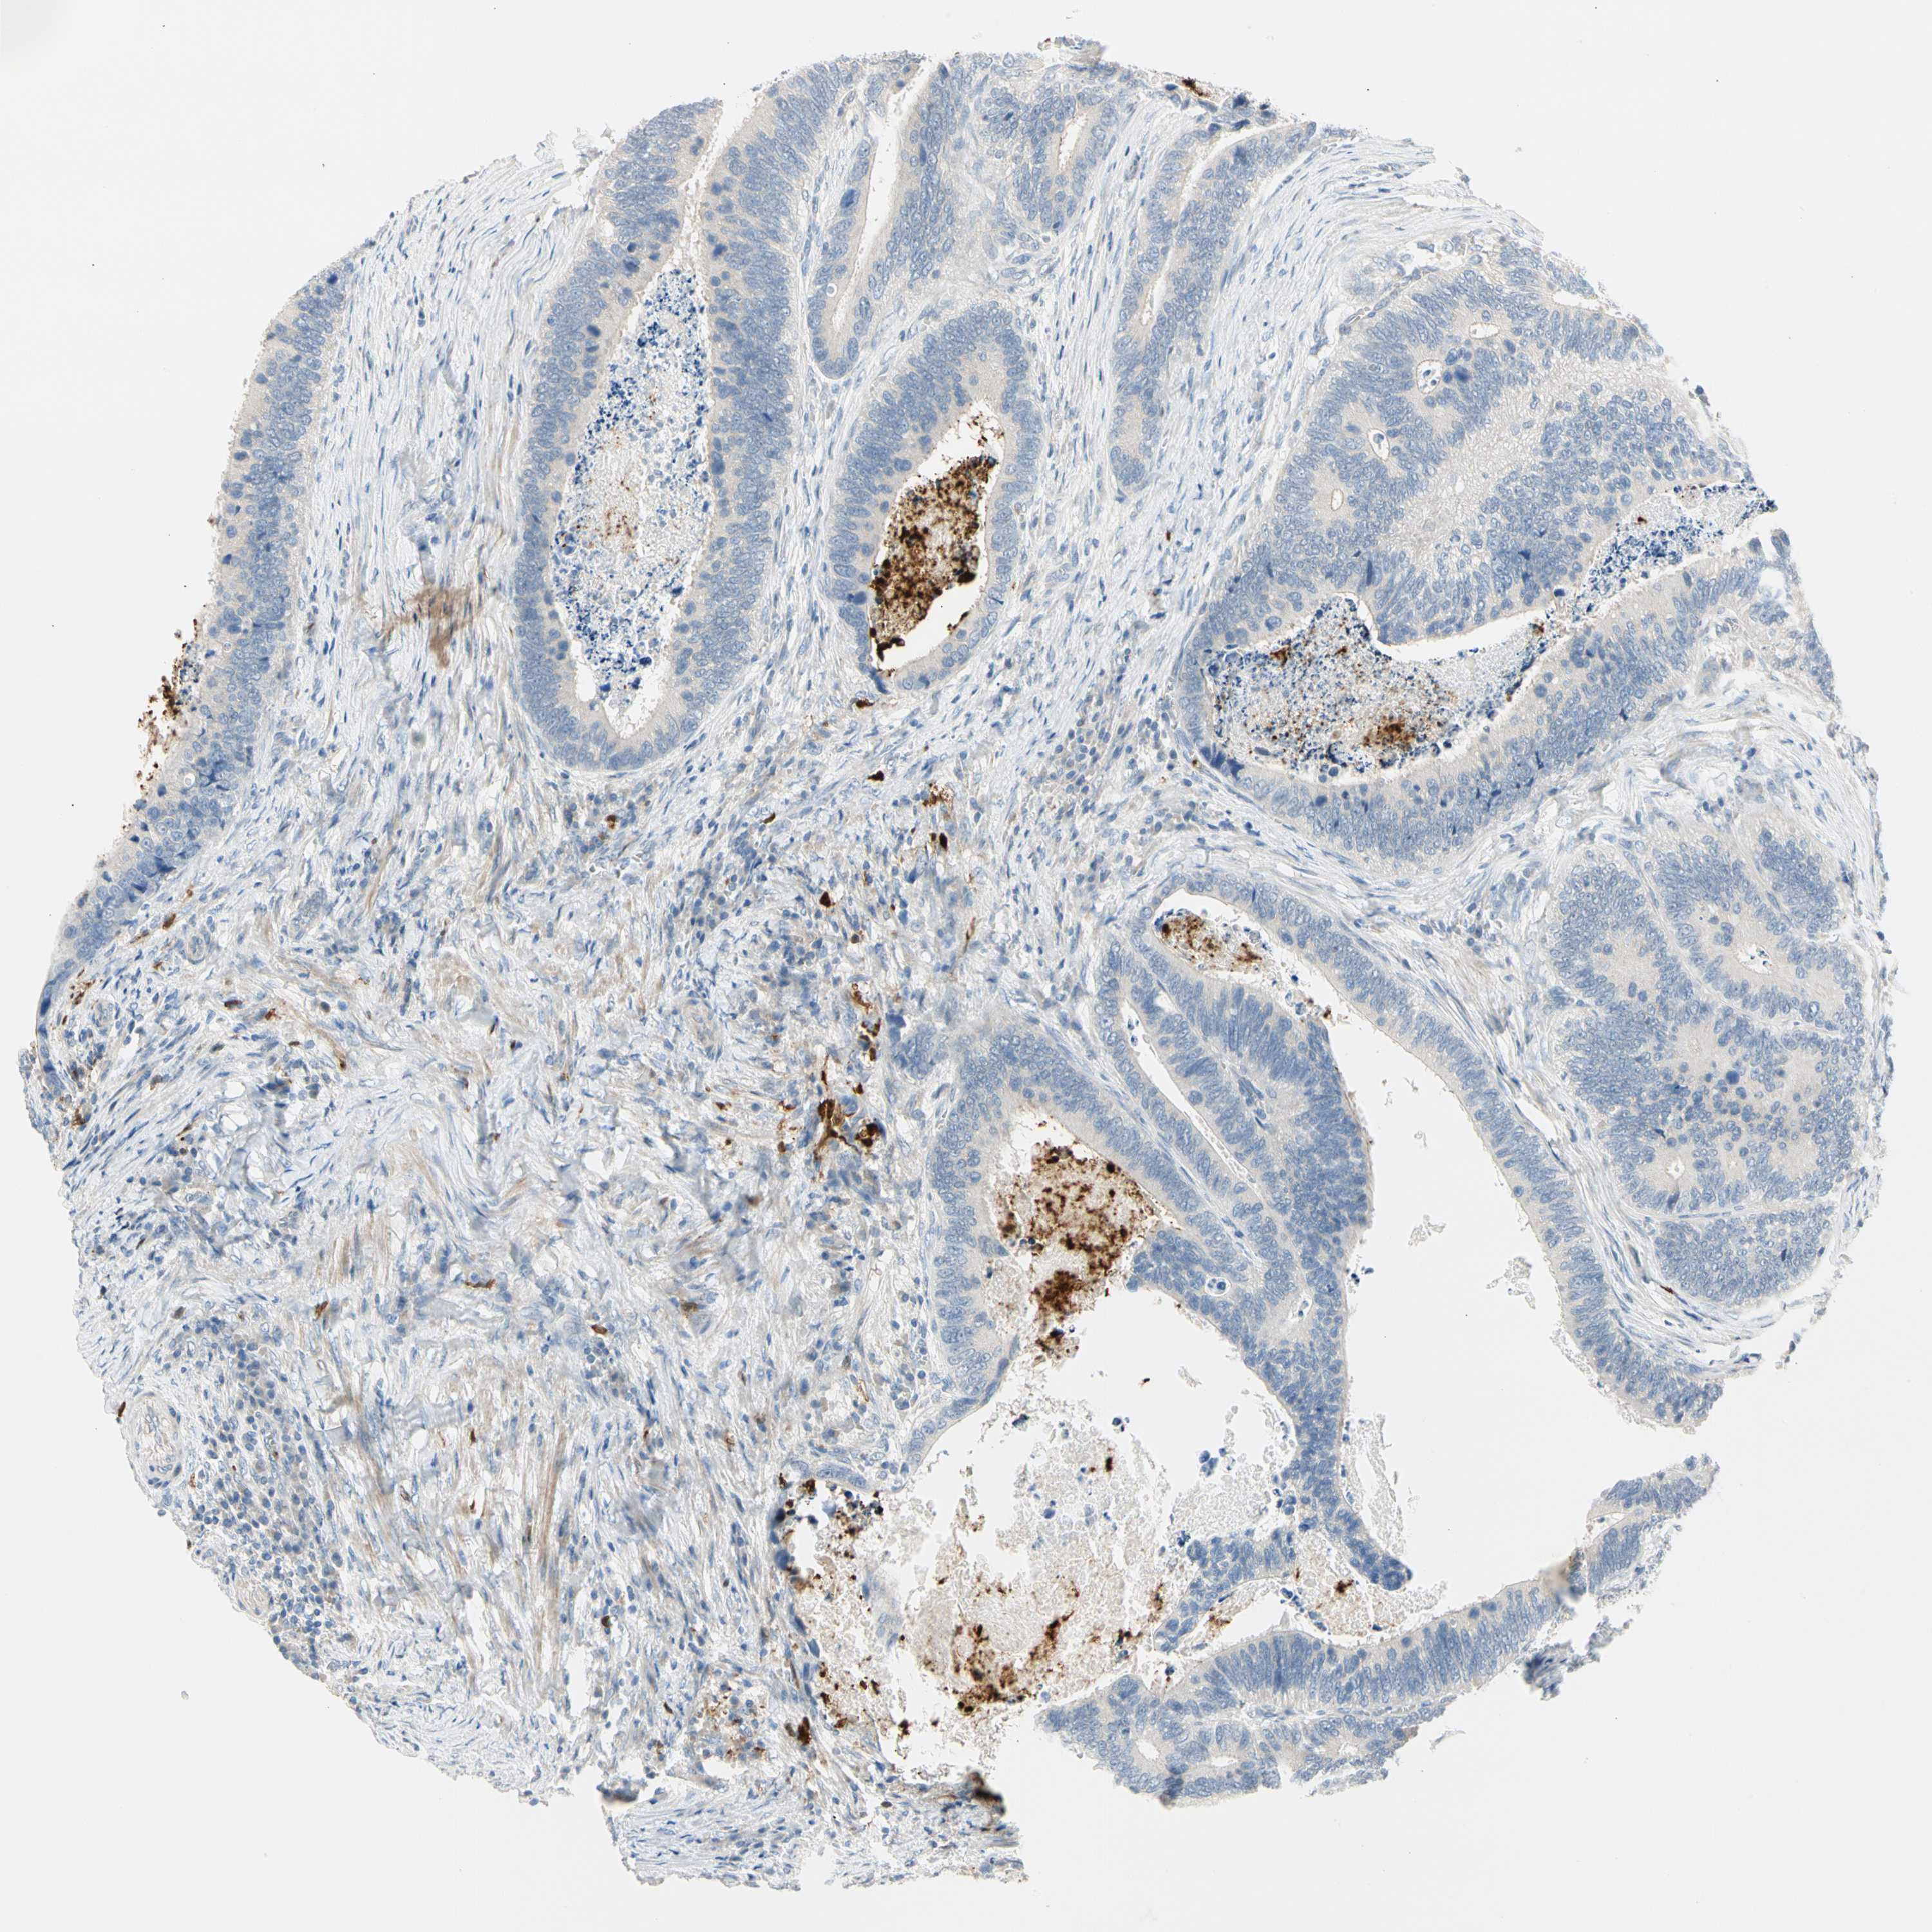

CANCER COLORECTAL CANCER Show tissue menu

Colorectal cancer

Human cancer

Colon adenocarcinoma